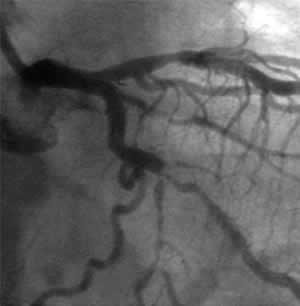

| Final CAG Findings:'01.9.18 LVG: asynergy (I&P), EF: 55%. CAG: #13 90% (ulceration), #14 99% |

![]() Control |